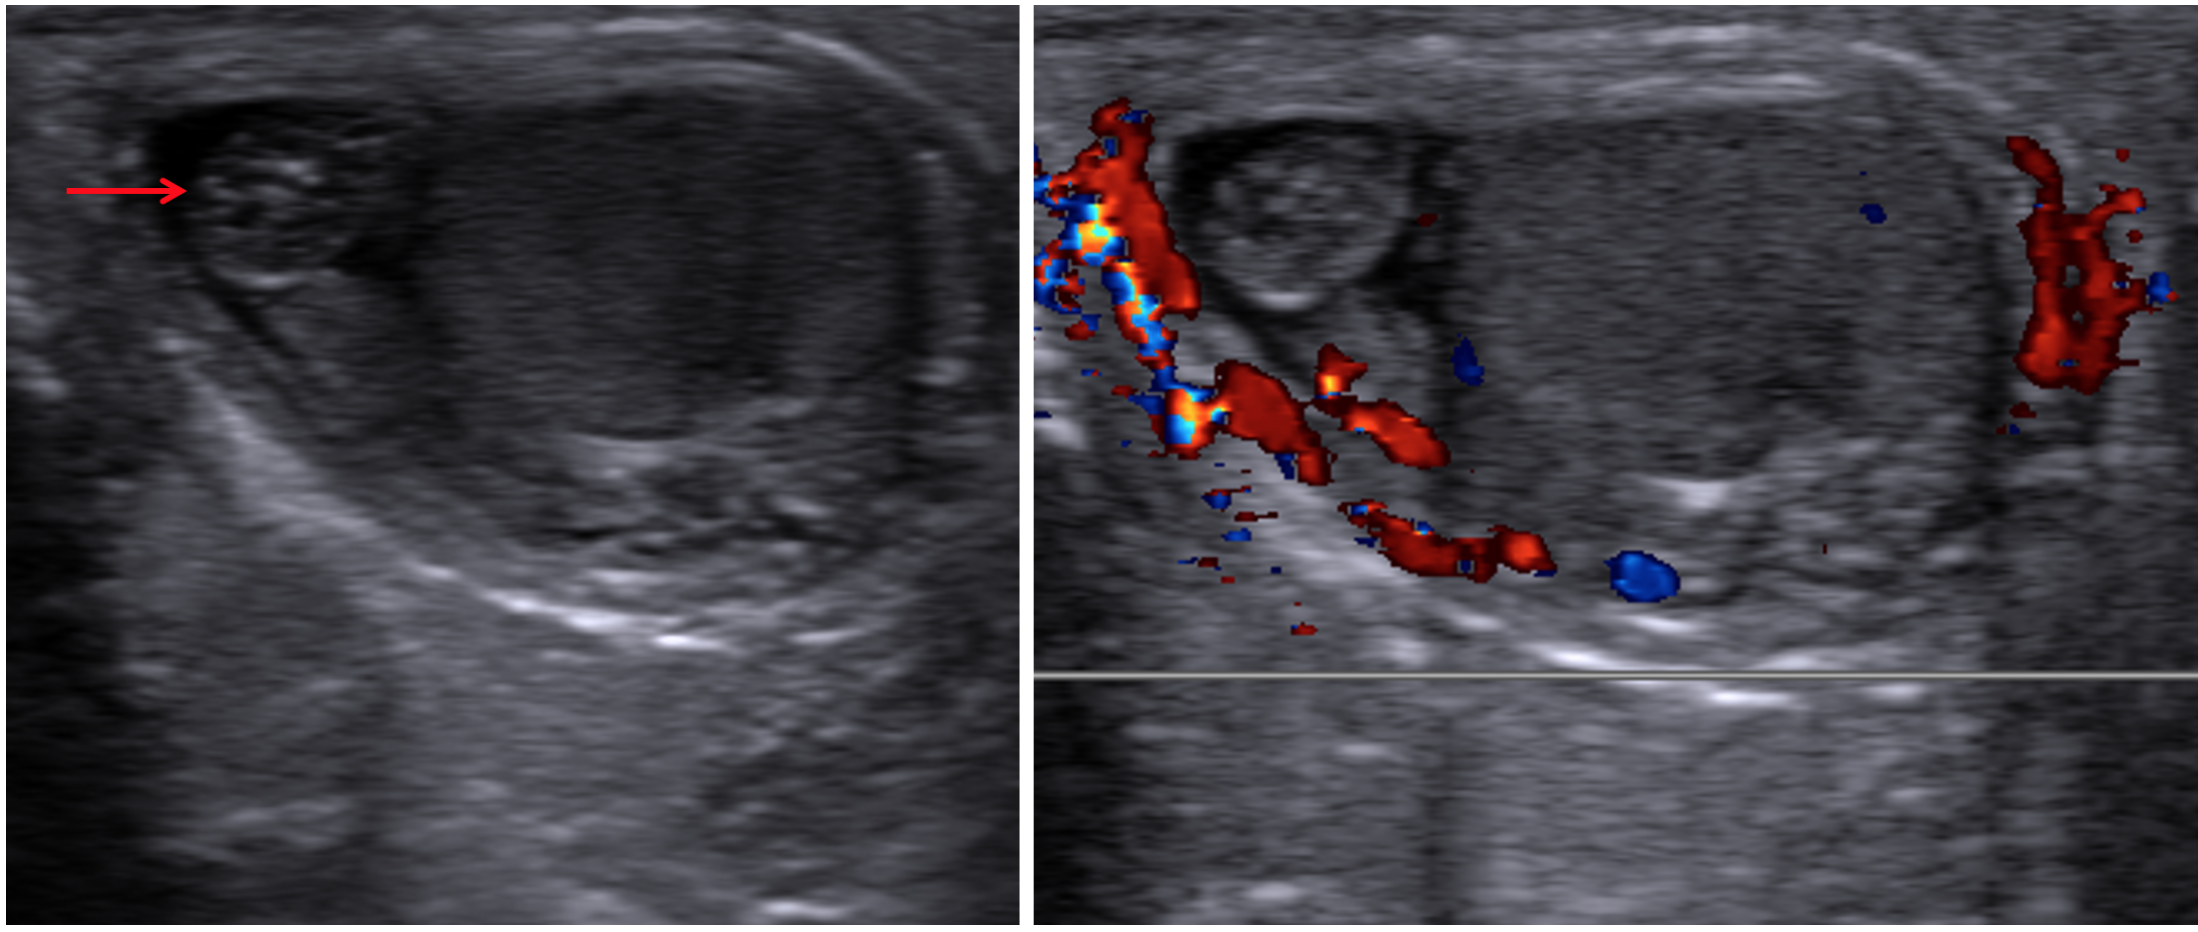

Epididymo-Orchitis

• Inflammation of the epididymis and testicle

• Presents as an enlarged and hyper-emic (increased blood flow) testicle/epididymis

• May also have

• Associated hydrocele

• Check to make sure it is not septated —> if septations are present = pyocele

• Hyper/hypo/heterogenous echotexture